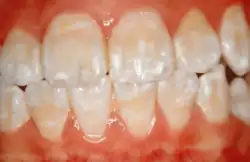

Diffuse opacities

White spot lesion can be seen across all teeth on the enamel. [21]

Diffuse opacities present as milky-white, chalky areas that spread across a tooth surface without clear borders as a result of a generalized decrease in the mineral content of the enamel which doesn’t involve localized breakdown.[22] Besides, the enamel may appear slightly porous and have a matte texture. Sadly, teeth with diffuse opacities may be aesthetically compromised even as they remain structurally intact and the condition is associated with mild systemic issues during enamel formation like nutritional deficiencies and mild illness.[23]